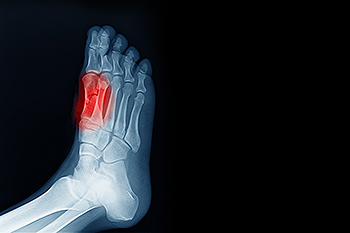

Sesamoiditis is a painful condition that affects the small sesamoid bones located beneath the big toe joint. These tiny bones act like pulleys, helping the tendons function smoothly during activities such as walking, running, and pushing off the ground. When the surrounding tissues become inflamed from overuse, repetitive impact, wearing high heeled shoes, or increased athletic activity, pain develops under the big toe and can make every step uncomfortable. The discomfort often worsens during weightbearing activities and may be accompanied by swelling or tenderness in the ball of the foot. A podiatrist can diagnose sesamoiditis through a physical exam and imaging, then recommend treatments that reduce pressure on the area. Care may include activity modification, offloading pads, custom orthotics, or supportive footwear. In more persistent cases, immobilization or other targeted therapies may be necessary. If you have pain under your big toe, it is suggested that you schedule an appointment with a podiatrist for a proper diagnosis and appropriate treatment.

Sesamoiditis is a condition of the foot that affects the ball of the foot. It is more common in younger people than it is in older people. It can also occur with people who have begun a new exercise program, since their bodies are adjusting to the new physical regimen. Pain may also be caused by the inflammation of tendons surrounding the bones. It is important to seek treatment in its early stages because if you ignore the pain, this condition can lead to more serious problems such as severe irritation and bone fractures.

In many cases the cause of toe pain is obvious, but in others, a podiatrist may want to use more advanced methods to determine the problem. These can range from simple visual inspections and sensation tests to X-rays and MRI scans. Prior medical history, family medical history, and any recent physical traumatic events will all be taken into consideration for a proper diagnosis.